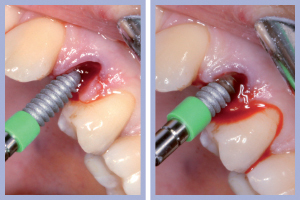

- Figg. 8a, b – Mappatura alveolare tramite sonda parodontale

- Figg. 9a, b – Preparazione del sito di destra

- Figg. 10a, b – Preparazione del sito di sinistra